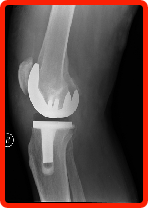

You may be interested to know what type of material the doctor will be placing in your body for your new joint. For knees, most of the joints are titanium, with plastic used as your new cartilage. For hips, there is also an option of ceramic on titanium. Based on the joint that you have selected, make sure you know what options exist & which works best to make your final decision.